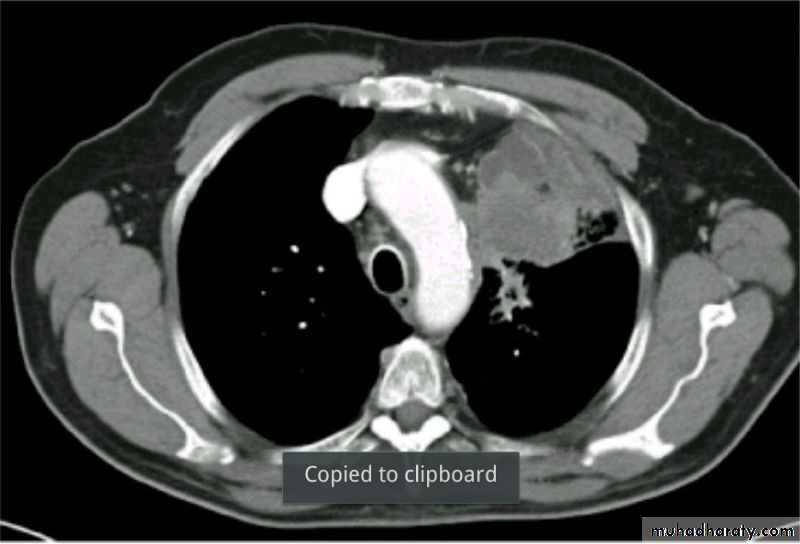

Severe dyspnea with shock

Tension PneumothoraxTension Pneumothorax